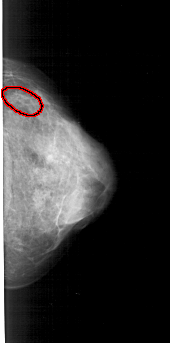

A_1570_1.RIGHT_MLO

RIGHT_CC LINES 4801 PIXELS_PER_LINE 2371 BITS_PER_PIXEL 12 RESOLUTION 43.5 OVERLAY

FILE: A_1570_1.RIGHT_CC.OVERLAY

TOTAL_ABNORMALITIES 1

ABNORMALITY 1

LESION_TYPE CALCIFICATION TYPE PLEOMORPHIC DISTRIBUTION CLUSTERED

ASSESSMENT 4

SUBTLETY 1

PATHOLOGY MALIGNANT

TOTAL_OUTLINES 1